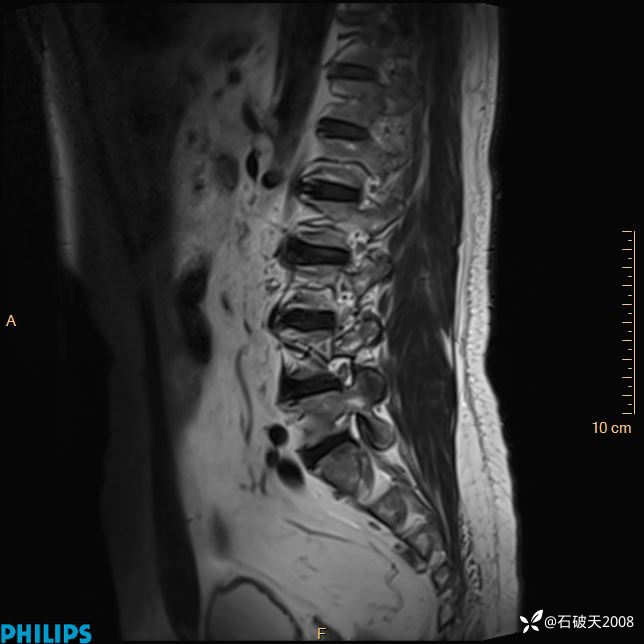

2023年3月份MRI影像

T2矢状位